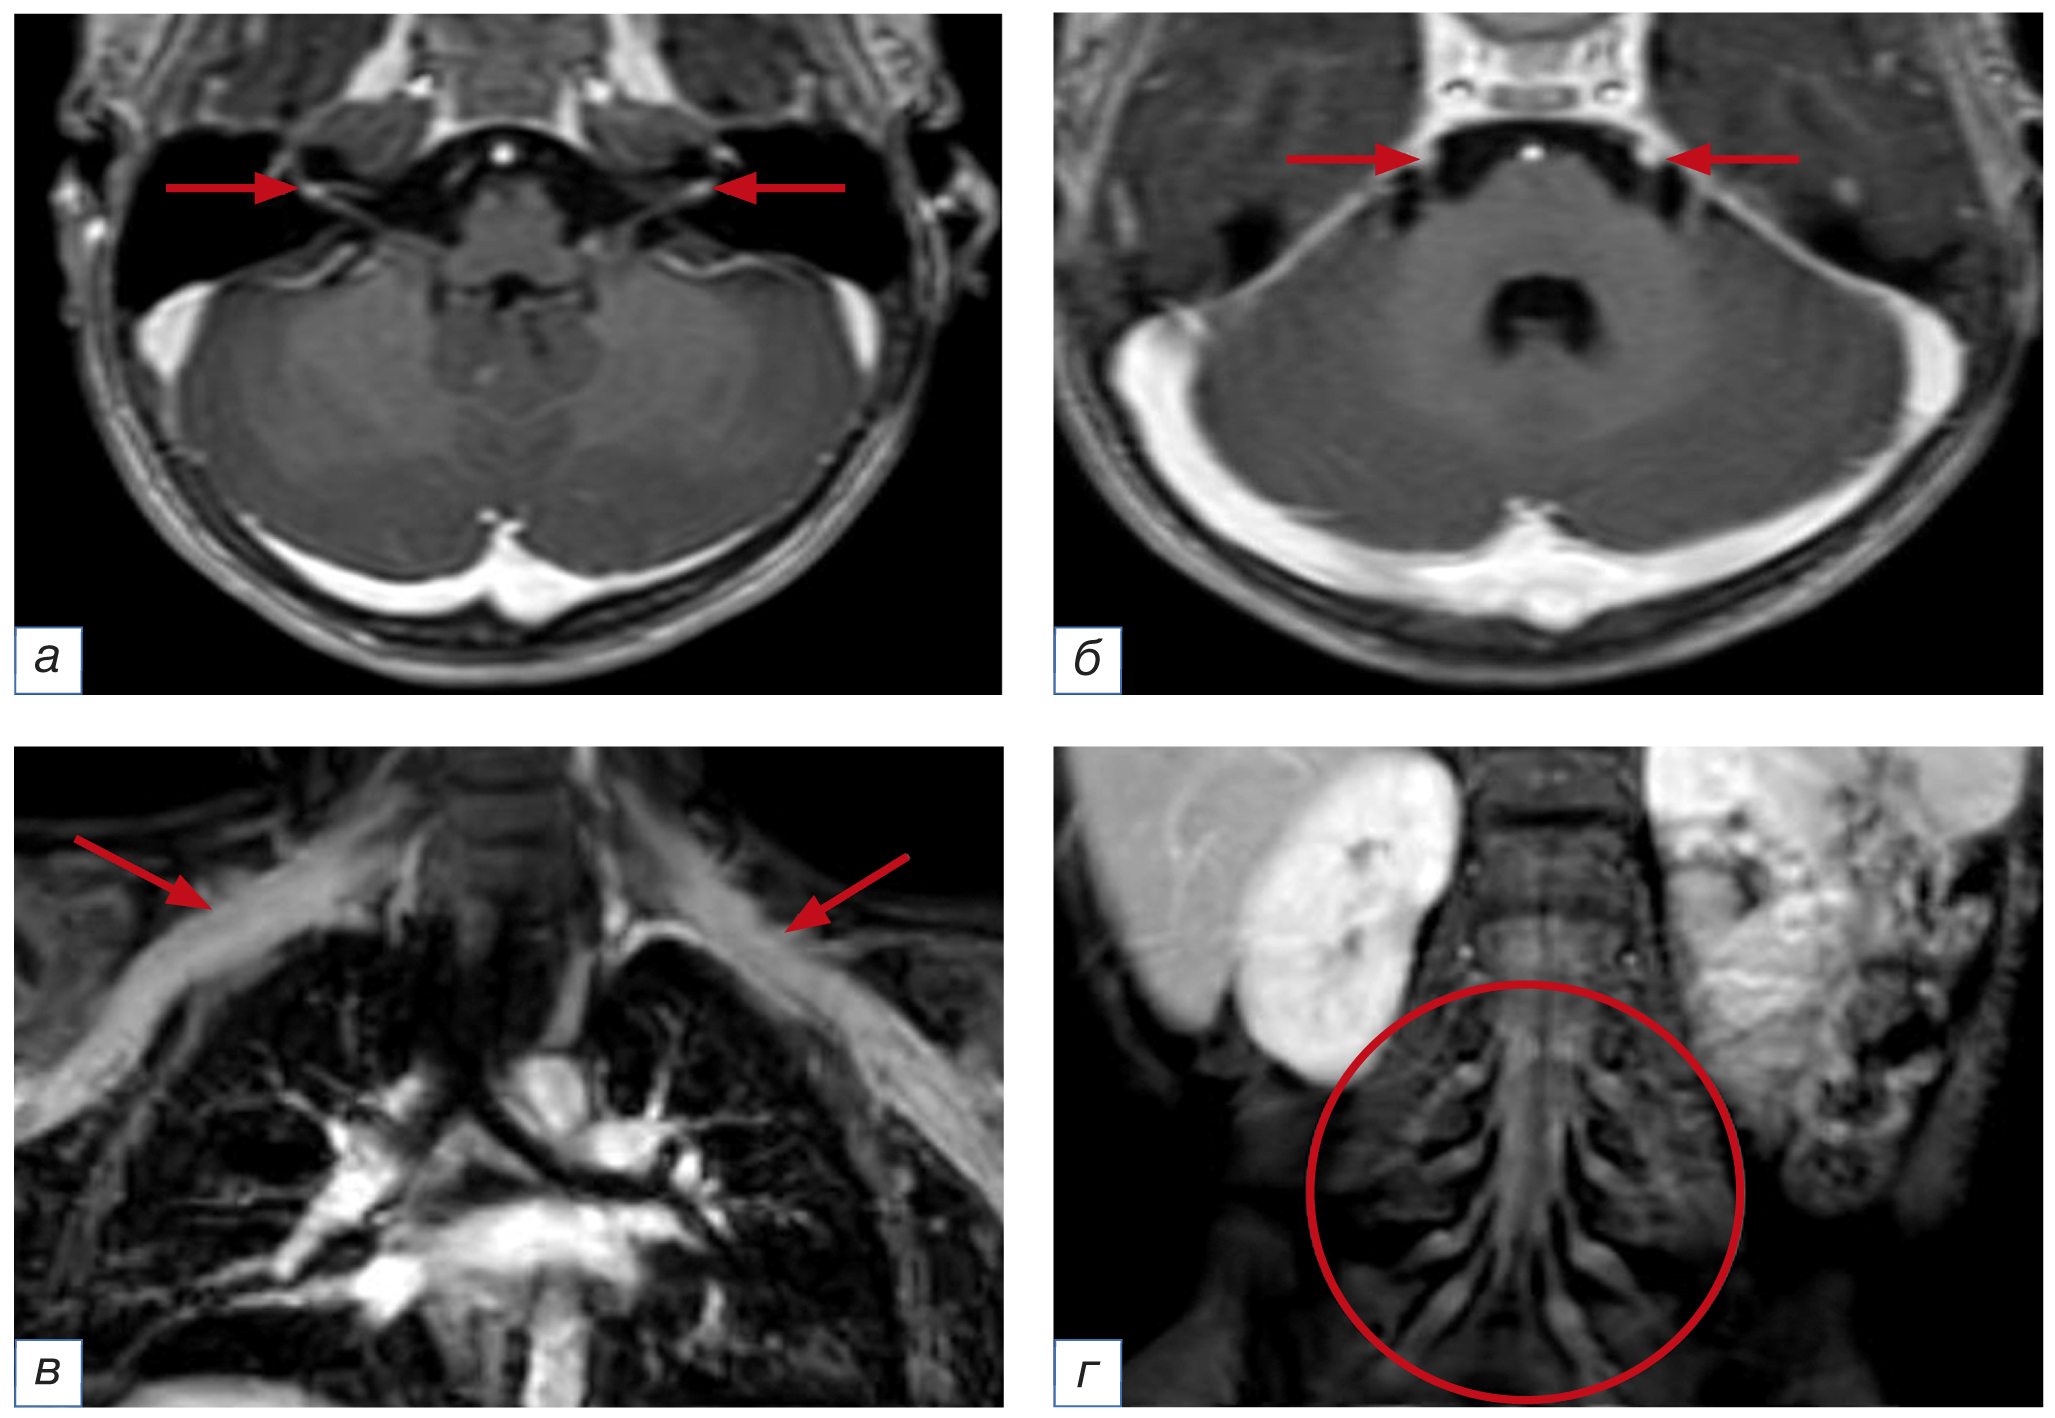

С дифференциально-диагностической целью после получения результатов электронейромиографии и ликворограммы для оценки распространённости, степени вовлечённости в воспалительный процесс краниальных и периферических нервов 02.11.2023 выполнена МРТ головного мозга и спинного мозга с внутривенным контрастным усилением. Обращало на себя внимание накопление контрастного вещества не только лицевыми нервами с двух сторон, но и тройничными нервами с двух сторон, корешками на уровне шейного, грудного отделов позвоночника, а также утолщёнными корешками конского хвоста. Кроме того, отмечались признаки накопления контрастного вещества в плечевых и пояснично-крестцовых сплетениях, что было расценено как вероятное проявление полиневрорадикулопатии и могло соответствовать синдрому Гийена–Барре. МРТ-признаков очаговых изменений в головном мозге не выявлено, однако имело место расширение внутренних ликворных пространств (рис. 1).

Рис. 1. Магнитно-резонансная томография головного мозга, плечевых и пояснично-крестцовых сплетений с внутривенным контрастированием. МР-признаки повышенного накопления контрастного вещества: а — лицевыми нервами на уровне внутреннего слухового прохода с обеих сторон; б — тройничными нервами в цистернальных отделах с обеих сторон; в — плечевыми сплетениями; г — поясничными и крестцовыми сплетениями

Fig. 1. Magnetic resonance imaging of the brain, brachial and lumbosacral plexuses with intravenous contrast. MR-signs of increased accumulation of contrast agent: а — facial nerves at the level of the internal auditory canal on both sides; б — trigeminal nerves in the cisternal sections on both sides; в — brachial plexuses; г — lumbar and sacral plexuses